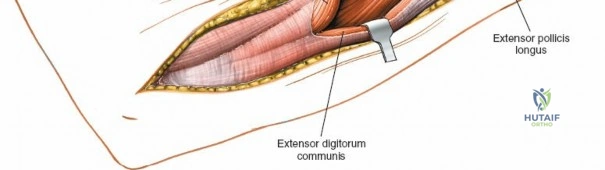

Deep Surgical Dissection: Exposing the Proximal Third

Exposing the proximal third of the radius requires extreme vigilance due to the proximity of the posterior interosseous nerve. The key anatomical landmark here is the insertion of the biceps tendon. Follow the biceps tendon distally to its insertion on the bicipital tuberosity of the radius. A small bursa lies just lateral to the tendon; incise this bursa to gain initial access to the proximal radial shaft. Because the radial artery lies superficial and medial to the tendon at this level, all deep dissection must remain strictly lateral to the biceps tendon.

The proximal radius is draped by the supinator muscle. The PIN passes directly through the belly of the supinator. To protect the nerve, the forearm must be fully supinated. Supination dynamically rotates the radius, carrying the insertion of the supinator anteriorly and simultaneously displacing the PIN laterally and posteriorly, safely away from the surgical field.

With the forearm fully supinated, identify the broad insertion of the supinator on the anterior aspect of the radius. Incise the supinator directly along the line of its insertion onto the bone. It is critical to detach the muscle by dividing its insertion sharply at the bone, rather than splitting the muscle belly, which would risk cutting the PIN.

Proceed with strict subperiosteal dissection, elevating the supinator laterally off the bone. This is one of the rare instances in orthopedic surgery where the safety gained by staying in a subperiosteal plane completely outweighs the theoretical vascular damage to the bone caused by periosteal stripping. The elevated supinator muscle belly now acts as a protective cushion for the PIN.

Retractor Placement and Fixation Technique

Once the proximal radius is exposed, great care must be taken with retractor placement. Never place Hohmann or levering retractors blindly around the posterior surface of the radial neck. Because the PIN may touch the bone posteriorly in up to 25% of patients, a posteriorly placed retractor can easily crush the nerve against the radial cortex. Instead, use gentle right-angle retractors or place retractors only on the anterior and lateral aspects of the bone, utilizing the elevated supinator as a shield.

For fracture fixation, a dynamic compression plate or locking compression plate is applied to the volar surface of the radius. The volar surface provides a flat, mechanically advantageous surface for plating and allows for excellent soft tissue coverage by the overlying muscle bellies upon closure. Ensure that the natural radial bow is meticulously restored during reduction to guarantee full postoperative pronation and supination.